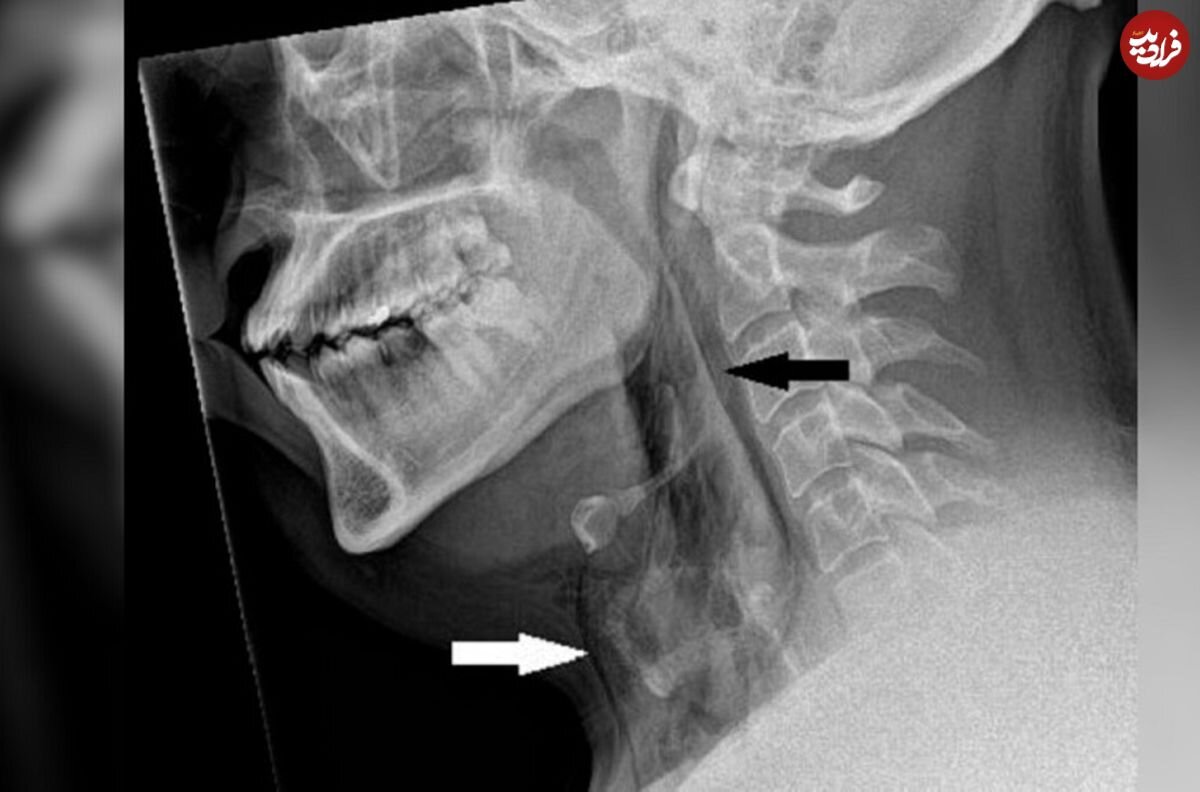

عکسبرداری با اشعه ایکس از گردن نشان داد مرد مبتلا به آمفیزم زیرپوستی است، بیماریای که در آن، هوا زیر عمیقترین لایههای بافت زیر پوست گیر میکند. توموگرافی کامپیوتری (سیتیاسکن) نشان داد پارگی بین استخوانهای سوم و چهارم یا مهرههای گردن او رخ داده است. هوا نیز در فضای قفسهسینه بین ریههای او جمع شده بود.

پزشکان به این نتیجه رسیدند که پارگی ناشی از افزایش سریع فشار در نای هنگام عطسه با بینی فشرده و دهان بسته است.